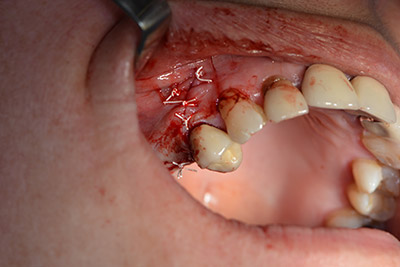

The next step was the sinus floor elevation with simultaneous implantation. The Implantmed also had a presetting at the first position for the buccal fenestration of the maxillary sinus wall.

The fenestration was prepared at 35,000 rpm and then the nasal mucosa were prepared in the cranial direction (Fig. 13 to 14).

preparation of the nasal mucosa

Image 13

Inclined drilling

Image 14